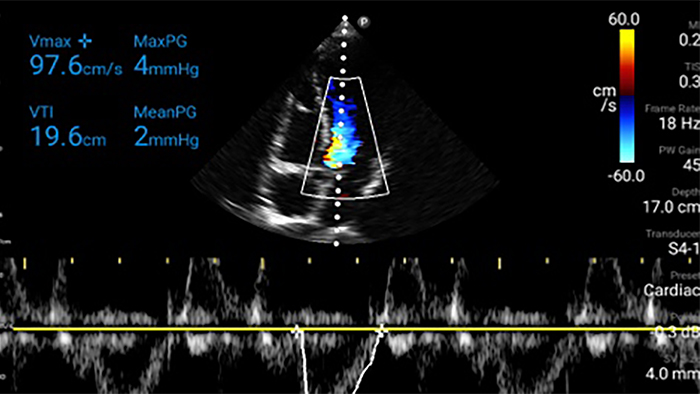

Jede Sekunde zählt in der Kardiologie

Herzinfarktpatienten benötigen unmittelbare Versorgung. Mit den kardiologischen Presets von Lumify können Patienten schneller diagnostiziert werden, um ihre Prognose zu verbessern.